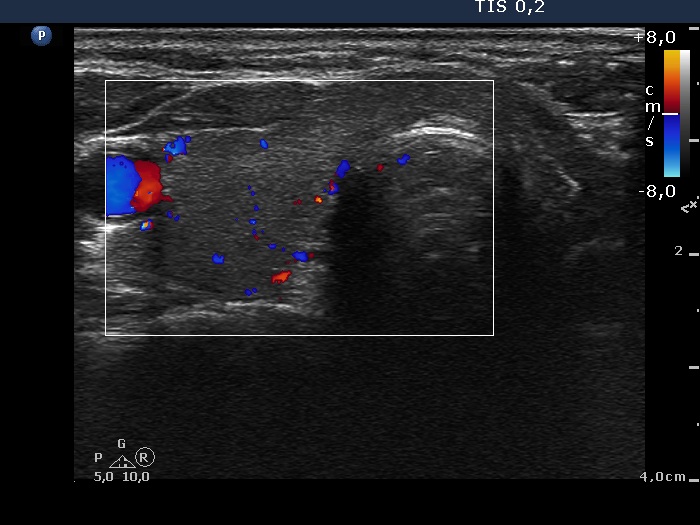

Ultrasonography. The right thyroid was moderately hypoechogenic without any circumscribed lesions. The left thyroid was removed. There were several enlarged lymph nodes in the right submandibular area. The largest one presented two discrete, more hypoechogenic intranodal lesions and a regular hilum.

Comment. This is an unusual case, the nodes (particularly those presented in the video) seem to be benign, reactive-type ones.